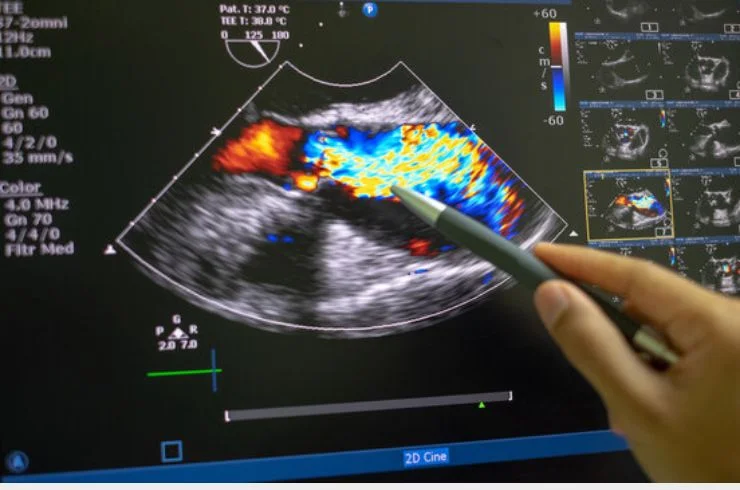

2-D-Echo

A 2-D Echo is an ultrasound test that provides real-time images of the heart, helping diagnose structural abnormalities, valve issues, and overall heart function.